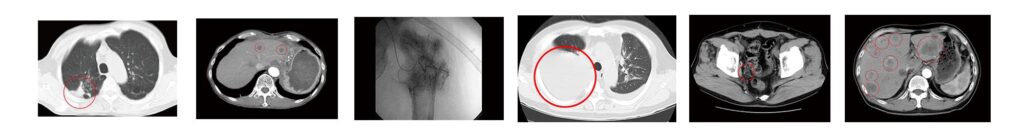

17) 胃がん症例①②③

(※)エビデンス 治療担当・院長:宇野克明の研究/臨床実績。がん免疫治療の研究/臨床応用(外来診療)開始以来、およそ29,000例の治療経験症例を有しています。1997年10月24日〜2023年10月31日。